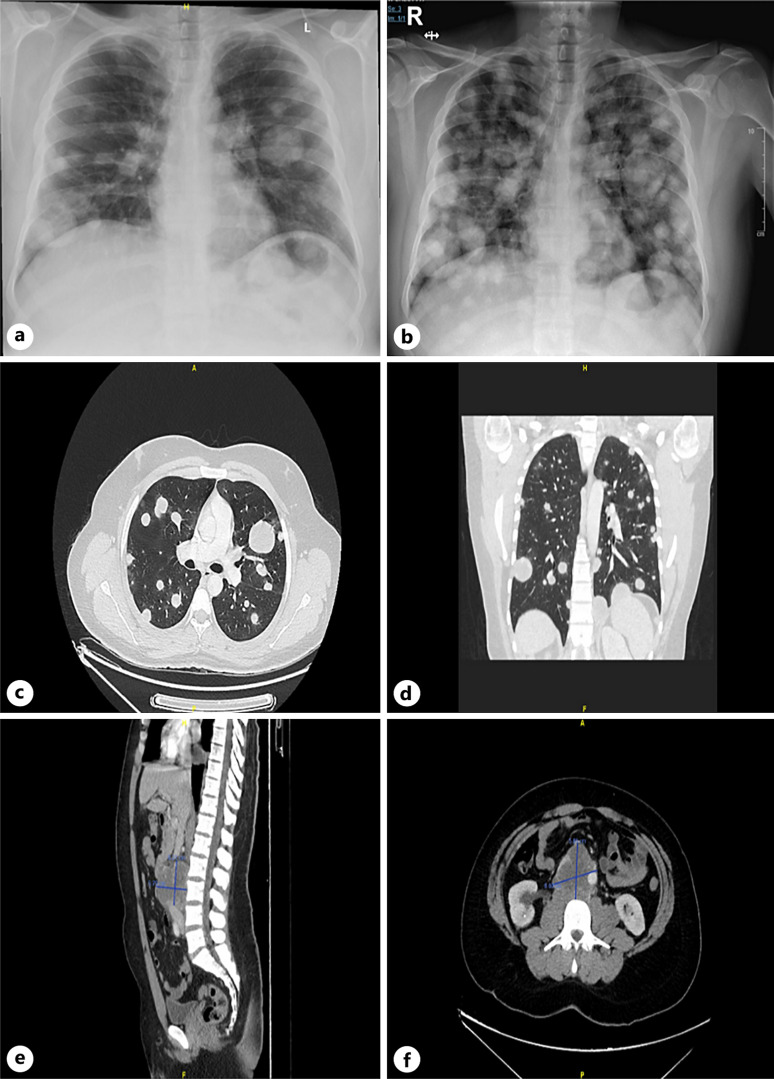

Case presentation: A 31-year-old male presented with progressive shortness of breath, cough, and hemoptysis for over a month. Initial imaging revealed multiple pulmonary nodules and a large necrotic retroperitoneal mass, along with liver metastases. The patient's β-human chorionic gonadotropin (β-hCG) levels were markedly elevated, raising suspicion of choriocarcinoma, subsequently confirmed through biopsy. Given the rapid clinical deterioration, chemotherapy with cisplatin and etoposide was initiated. The patient responded well to treatment, with a significant reduction in tumor and metastasis size. Over 30 months of follow-up, the patient showed continued clinical improvement with no evidence of disease recurrence.